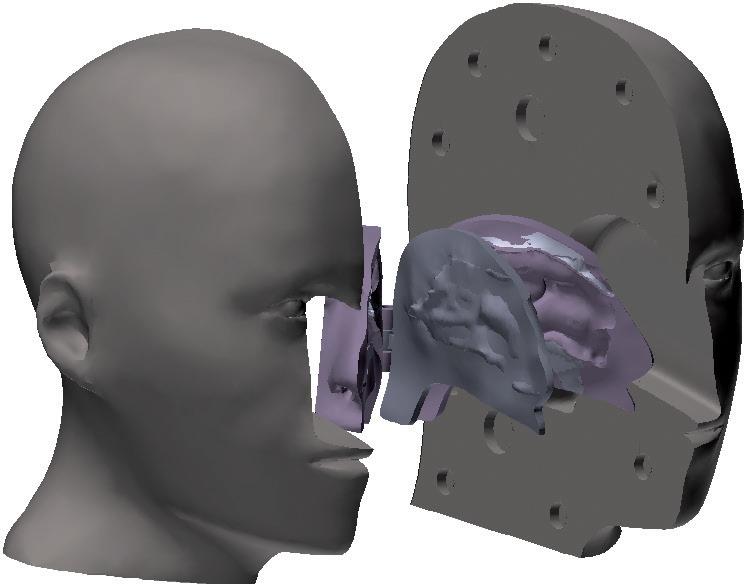

Generally, biologics are therapeutic proteins derived from living systems (such as bacteria, yeast, plants or animals) or blood that differ from “small molecules”, which are synthetic, or plant derived (see Figure 1). Examples of biologics include vaccines, growth factors, monoclonal antibodies and immune modulators. With their high target specificity and comparatively low toxicity, biologics are one of the fastest-growing therapeutic classes in the pharmaceutical industry.

Figure 1: Comparison of three different classes of biologic drugs with a typical small molecule. (Adaptation from Revers L & Furczon E, Canadian Pharmacists Journal, 2010.)